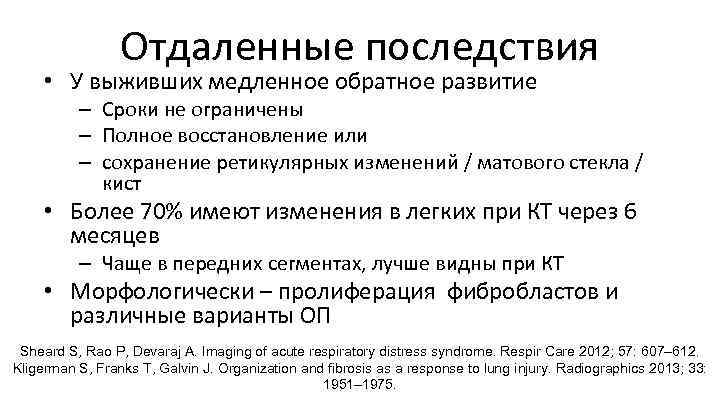

Отдаленные последствия • У выживших медленное обратное развитие – Сроки не ограничены – Полное восстановление или – сохранение ретикулярных изменений / матового стекла / кист • Более 70% имеют изменения в легких при КТ через 6 месяцев – Чаще в передних сегментах, лучше видны при КТ • Морфологически – пролиферация фибробластов и различные варианты ОП Sheard S, Rao P, Devaraj A. Imaging of acute respiratory distress syndrome. Respir Care 2012; 57: 607– 612. Kligerman S, Franks T, Galvin J. Organization and fibrosis as a response to lung injury. Radiographics 2013; 33: 1951– 1975.